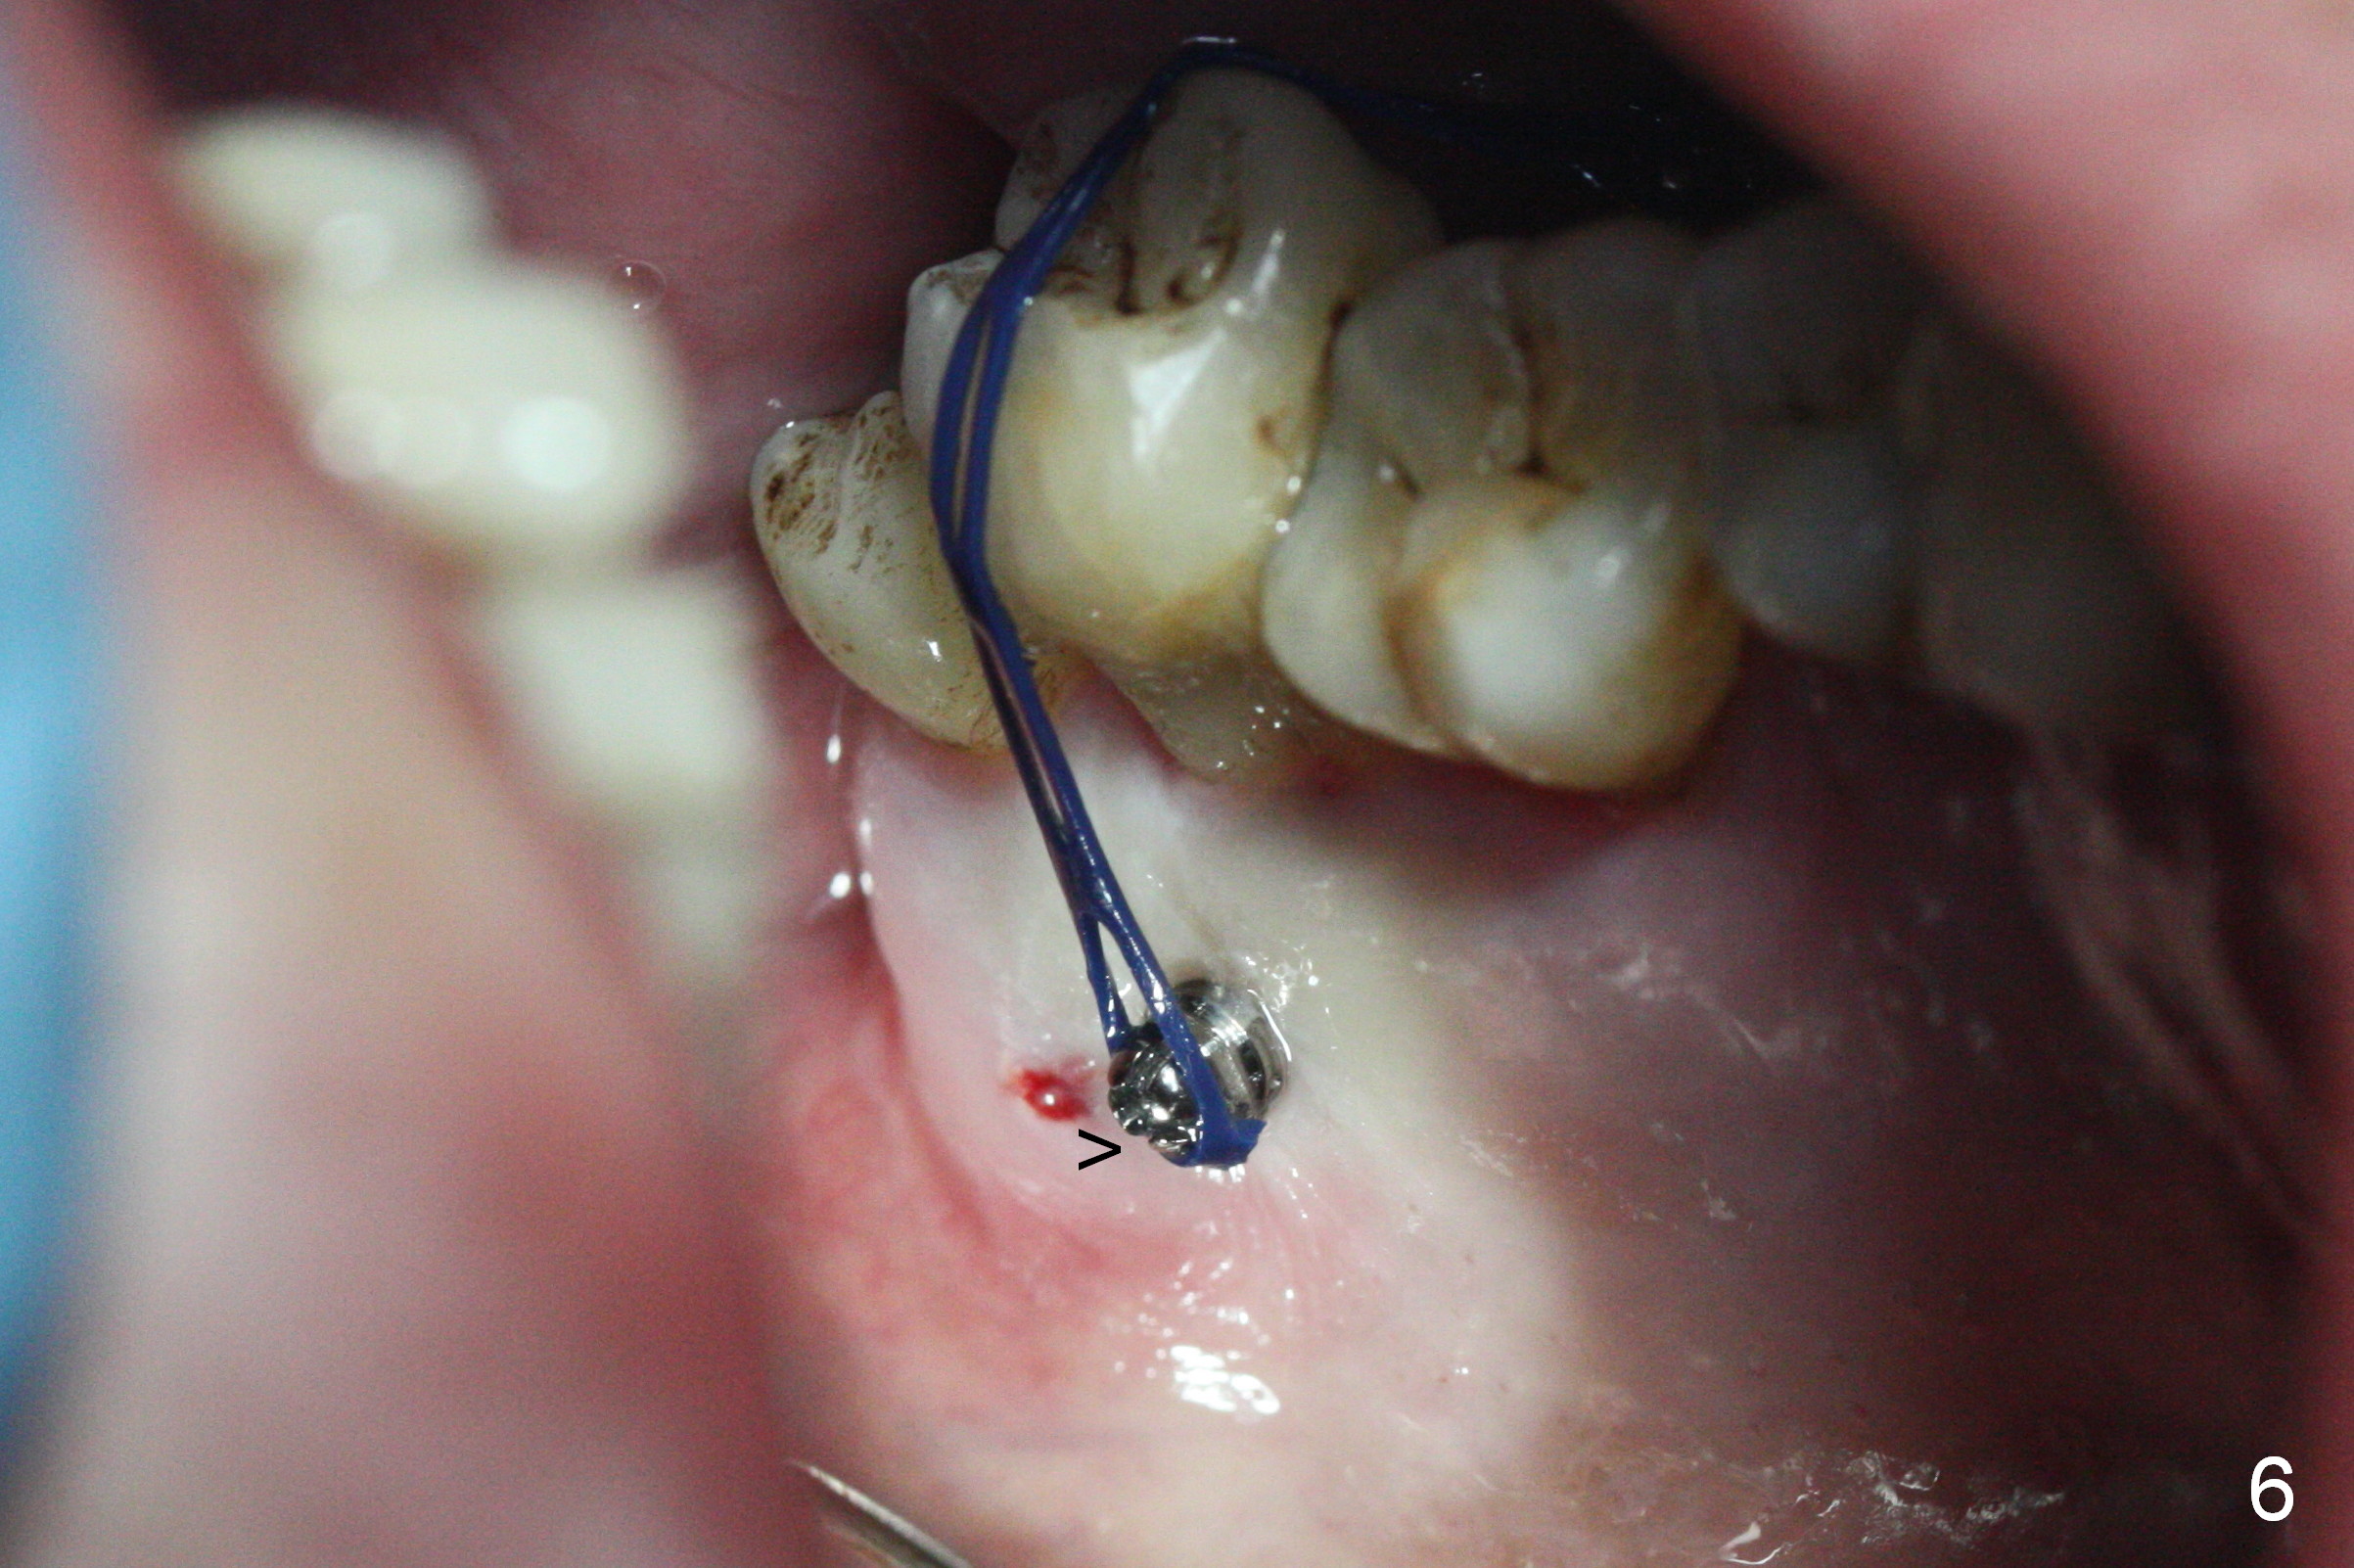

Two days post #31 implant placement, the patient returns for orthodontic intrusion of the tooth #2 with mini-implants (Fig.1). The palatal cusps have been trimmed (Fig.2 ^), since they almost contact a healing abutment at #31(*, Fig.3). Two mini-implants are to be placed mesiobuccal and distopalatal to the affected tooth. After minimal injection of Lidocaine, a 1.6x6 mm Tomas implant is placed in full length mesially (Fig.4), while the other (1.6x8 mm) half way (Fig.4). Following change in implant site mesially (Fig.6 >), the implant is half inserted (Fig.5). It appears that the tip of the distal implant is toward the tooth #1 (Fig.5). After withdrawing the implant partially, it is re-directed to apparently ideal trajectory (Fig.7). Ideally the mesial implant (Fig.8) should have been placed partially initially (Fig.4,5,7) so that the trajectory could have been able to be changed.

The buccal implant becomes loose in 2-3 months. When the wound heals (Fig.9 <), a 1.6x`10 mm implant is placed with the help of PAs for trajectory (Fig.10,11) and in the nonkeratinized gingiva (higher, the crestal bone may have been traumatized by previous implant placement, Fig.12). Two months later, the tooth #2 is partially intruded (Fig.13). A provisional (Fig.14 P) is fabricated in the osteointegrated implant at #31 with supraocclusion so that the remaining dentition has no occlusal contact (*). The periodontally compromised tooth #2 becomes in buccoversion in 2 months. The provisional is removed, while a lingual button is placed in the buccal surface of the tooth #2 (Fig.15). With power chain attached to the lingual mini-implant, the tooth #2 is lingualized in 2 months. The provisional and the implants are reused for final intrusion (Fig.16). The treatment is nearly 11 months. The buccal implant, although placed in the movable mucosa, remains stable and healthy (Fig.17). The tooth #1, as a guiding plane (to prevent #2 from distalization during intrusion), is not extracted after intrusion is completed.